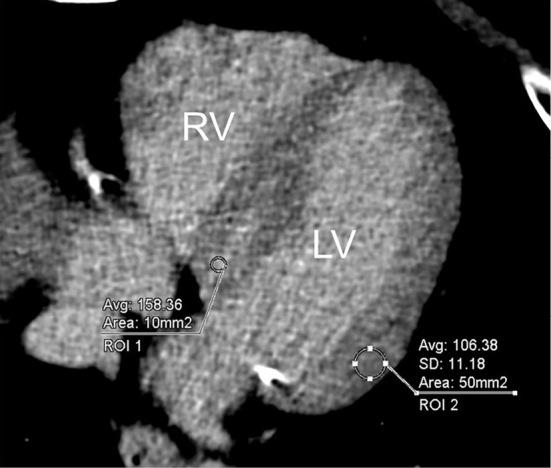

单能量256排多层螺旋CT联合深度学习图像重建在评估心肌纤维化中的强大诊断性能

Strong Diagnostic Performance of Single Energy 256-row Multidetector Computed Tomography with Deep Learning Image Reconstruction in the Assessment of Myocardial Fibrosis.

Objective Although magnetic resonance imaging (MRI) is the gold standard for evaluating abnormal myocardial fibrosis and extracellular volume (ECV) of the left ventricular myocardium (LVM), a similar evaluation has recently become possible using computed tomography (CT). In this study, we investigated the diagnostic accuracy of a new 256-row multidetector CT with a low tube-voltage single energy scan and deep-learning-image reconstruction (DLIR) in detecting abnormal late enhancement (LE) in LVM. Methods We evaluated the diagnostic performance of CT for detecting LE in LVM and compared the results with those of MRI as a reference. We also measured the ECV of the LVM on CT and compared the results with those on MRI. Materials We analyzed 50 consecutive patients who underwent cardiac CT, including a late-phase scan and MRI, within three months of suspected cardiomyopathy. All patients underwent 256-slice CT (Revolution APEX; GE Healthcare, Waukesha, USA) with a low tube-voltage (70 kV) single energy scan and DLIR for a late-phase scan. Results In patient- and segment-based analyses, the sensitivity, specificity, and accuracy of detection of LE on CT were 94% and 85%, 100% and 95%, and 96% and 93%, respectively. The ECV of LVM per patient on CT and MRI was 33.0±6.2% and 35.9±6.1%, respectively. These findings were extremely strongly correlated, with a correlation coefficient of 0.87 (p<0.0001). The effective radiation dose on late-phase scanning was 2.4±0.9 mSv. Conclusion The diagnostic performance of 256-row multislice CT with a low tube voltage and DLIR for detecting LE and measuring ECV in LVM is credible.

摘要

目的 尽管磁共振成像(MRI)是评估左心室心肌(LVM)异常心肌纤维化和细胞外容积(ECV)的金标准,但最近使用计算机断层扫描(CT)也能够进行类似评估。在本研究中,我们调查了一种新型256排多探测器CT在低管电压单能量扫描和深度学习图像重建(DLIR)下检测LVM异常延迟强化(LE)的诊断准确性。方法 我们评估了CT检测LVM中LE的诊断性能,并将结果与作为参考的MRI结果进行比较。我们还在CT上测量了LVM的ECV,并将结果与MRI上的结果进行比较。材料 我们分析了50例连续的患者,这些患者在疑似心肌病的三个月内接受了心脏CT检查,包括晚期扫描和MRI检查。所有患者均接受256层CT(Revolution APEX;GE Healthcare,美国威斯康星州沃基沙)的低管电压(70 kV)单能量扫描和晚期扫描的DLIR。结果 在基于患者和节段的分析中,CT检测LE的敏感性、特异性和准确性分别为94%和85%、100%和95%、96%和93%。CT和MRI上每位患者LVM的ECV分别为33.0±6.2%和35.9±6.1%。这些发现具有极强的相关性,相关系数为0.87(p<0.0001)。晚期扫描的有效辐射剂量为2.4±0.9 mSv。结论 具有低管电压和DLIR的256排多层CT在检测LVM中的LE和测量ECV方面的诊断性能是可靠的。